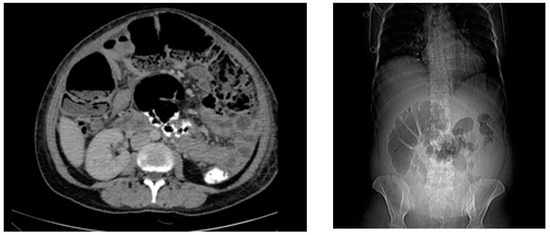

Figure 2.

Abdominal CT at presentation indicating colonic dilatation with colonic wall thickening was consistent with ileus without obstructing mass or collection.

The patient appeared critically ill, and she was febrile (38.4 °C); her blood pressure was 100/55 mmHg, and she was tachycardic (118 bpm). The physical examination was significant for diffuse pain on all four quadrants to palpation, hypoactive bowel sounds, and severe abdominal distension without rebound tenderness consistent with acute abdomen with prolonged postoperative ileus. There was no discharge from the site of incision. At presentation, laboratory tests were remarkable for anemia (Hgb = 7.7 g/dL) marked elevation in acute-phase reactants (CRP = 425 mg/L; procalcitonin = 0.33 ng/mL), and white blood cells with neutrophilic predominance (leukocytes: 14,100 cells/mm3; neutrophils: 85.4%). Abdominal CT was consistent with ileus without an obstructing mass or postoperative collection (Figure 2). Her recent obstetric history was unremarkable other than the administration of oral third-generation cephalosporin (cefdinir 600 mg q24h) for asymptomatic bacteriuria for five days on the 34th week of pregnancy. Postpartum, she had also used two days of cefdinir per oral as postoperative prophylaxis. After ruling out mechanical obstruction and surgical site infections, fulminant CDI was considered in the differential diagnosis based on the severity of the clinical picture, recent operation, hospitalization, and antibiotic use.